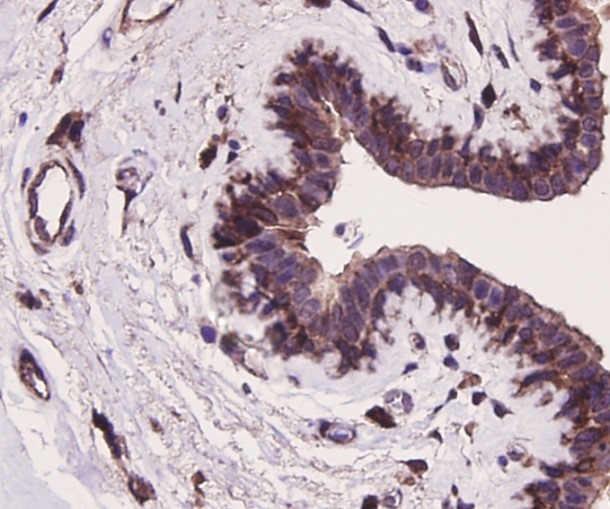

Fig3:

Immunohistochemical analysis of paraffin-embedded

human colon carcinoma tissue using anti-Bcl-2 rabbit

polyclonal antibody. Counter stained with hematoxylin.